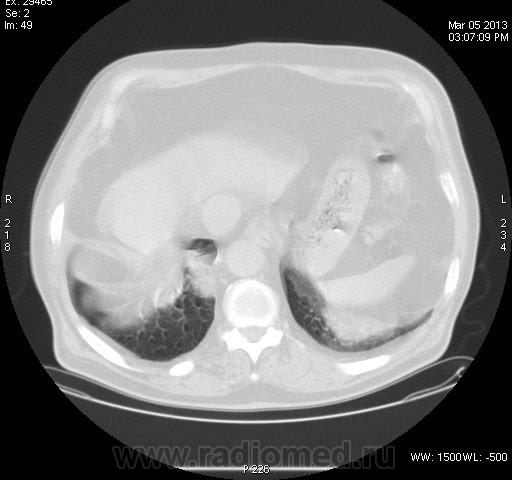

Непонятка КТ ОГК.

Задыхается, кашляет, Т-37, КТ "Cito!", рентгенограмм нет. В поликлинике закл.:" Двухстороння пневмония, МТС?"

Анализ изображений КТ исследования ОГК обязательно должен проводиться в двух окнах (легочном и медиастинальном). А в диф. плане, так еще  и с контрастированием. Есть ли возможность хотя бы увидеть изображения во втором режиме: для оценки участков консолидации, наличия кавтации, оценки л/узлов и средостения в целом...?

Не повезло больному. 11.03.2013г. умер в реанимации, сегодня только узнал. Причина смерти- множественные инфарт- пневмонии?!. Завтра выложу все, что найду. Я в шокеsurprise! Писал диссеминацию по типу септической + БАР.

Что говорить о контрастном КТ исследовании, если даже КТ-изображения данного пациента не выставлены во втором (медиастинальном) окне; была бы возможность оценки характера участков конолидации легочной ткани, состояния лимфатических узлов и средостения в целом.  Почему то никто не отметил наличие катеторов в верхней полой вене и правом желудочке сердца, что косвенно должно было навести на тромбоэмболический процесс. Конечно, в данном случае, КТ исследование с болюсным контрастированием помогло бы в правильной диагностике.